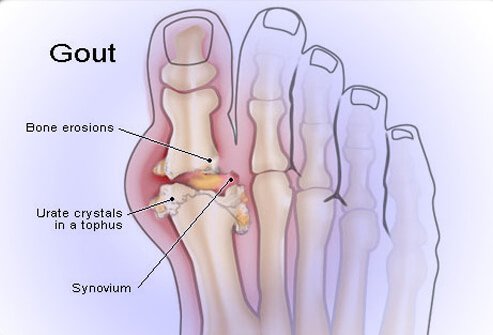

To understand how to treat gout we need to look at the chemical process occurring in the body when someone presents with gout. The pain one feels is largely due to the presence of uric acid crystals lingering in the blood, which tend to settle in our joints. The liver and kidneys are highly capable of processing the uric acid from our food and drink. However, if we load our bodies full of highly acidic foods, it can stress our organs, leaving uric acid crystals to float freely in our blood stream.

Foods that contribute highly to uric acid production tend to be the more acidic foods, such as red meats, sugar, caffeine, soda and alcohol. Beer is the worst type of alcohol for gout. People with diets high in acidic foods and low in alkaline foods, such as fruits and vegetables, tend to have higher levels of uric acid. When the body accumulates too much uric acid, it can even form bulbous growths on your joints just under your skin called tophi.